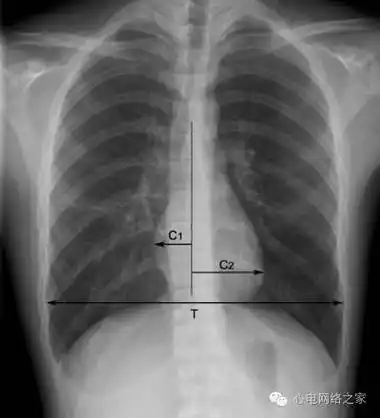

阅读x线胸片,这是一个靴形心脏的胸片.

shs具有特征性的x线表现,心影小而狭长,各弧度平滑,心膈间隙较宽,长轴